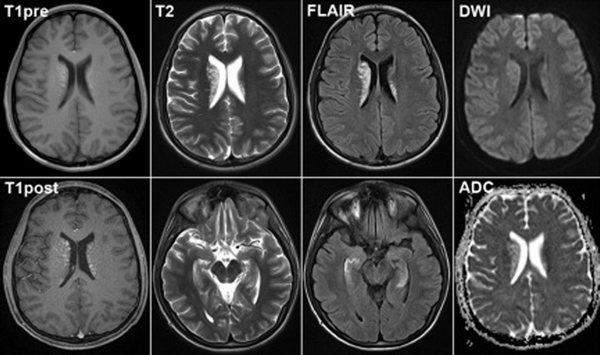

В магнитно-резонансной томографии (МРТ) визуализация тканей зависит от выбранного режима сканирования: T1, T2, FLAIR и DWI . Каждый режим подчеркивает определенные характеристики тканей, что позволяет лучше дифференцировать патологии. Вот основные особенности визуализации тканей в каждом режиме:

1. Режим T1:

• Жировая ткань: Яркая (гиперинтенсивная).

• Мозговое вещество: Серое вещество темнее, чем белое.

• Спинномозговая жидкость (СМЖ): Темная (гипоинтенсивная).

• Мышцы и паренхиматозные органы: Промежуточная интенсивность сигнала.

• Кости и воздух: Темные (гипоинтенсивные).

• Применение: Анатомическая визуализация, оценка кровоизлияний (в острой стадии), жировой ткани, контрастного усиления (например, при опухолях).

2. Режим T2:

• Спинномозговая жидкость (СМЖ): Яркая (гиперинтенсивная).

• Отек и воспаление: Яркие.

• Мозговое вещество: Белое вещество темнее, чем серое.

• Жировая ткань: Темнее, чем на T1.

• Применение: Выявление патологий с повышенным содержанием воды (отек, воспаление, опухоли, инфаркты).

3. Режим FLAIR (Fluid-Attenuated Inversion Recovery):

• Спинномозговая жидкость (СМЖ): Подавлена (темная), что позволяет лучше видеть патологии рядом с СМЖ.

• Мозговое вещество: Аналогично T2, но с подавлением сигнала от СМЖ.

• Применение: Выявление очаговых изменений вблизи желудочков мозга (например, при рассеянном склерозе, ишемических изменениях, энцефалите).

4. Режим DWI (Diffusion-Weighted Imaging):

• Ограничение диффузии: Области с ограниченной диффузией (например, при ишемии) выглядят яркими (гиперинтенсивными).

• Нормальные ткани: Промежуточная интенсивность сигнала.

• Применение:

Ранняя диагностика ишемического инсульта (в течение нескольких минут после начала).

Выявление абсцессов, опухолей с высокой клеточностью (например, лимфомы).

Оценка диффузных изменений в белом веществе мозга.